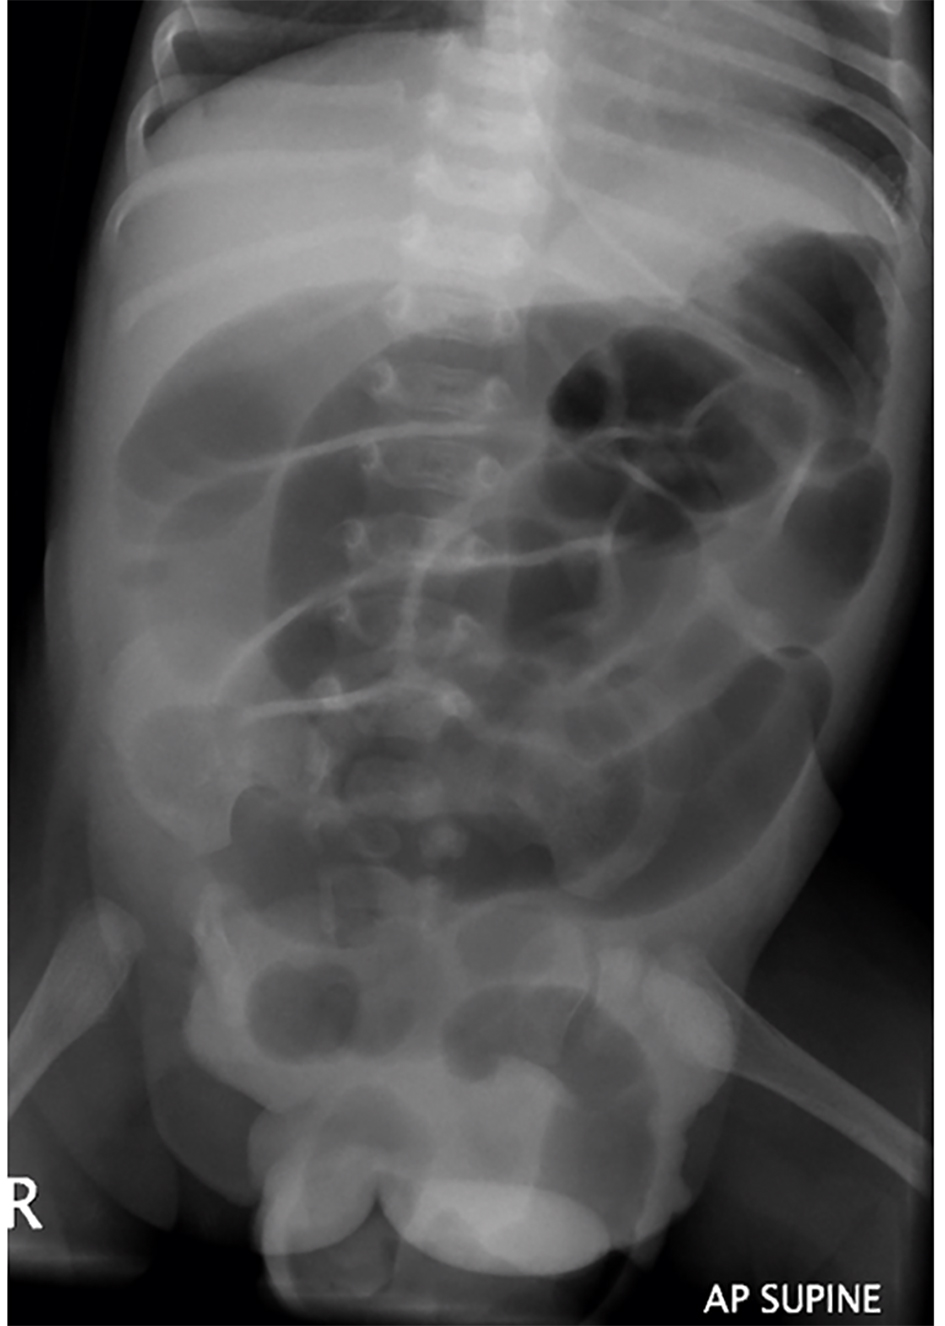

Chest radiograph showed clear lung fields (Fig. 1). Abdominal radiograph showed dilated bowel loops (Fig. 2). There were no signs of sepsis on chest radiograph and NEC on abdominal radiograph. As she continued to deteriorate, she was referred to and transferred to us on the third day of admission for small bowel obstruction with bowel ischemia.

![]() Click for large image | Figure 2. Abdominal radiograph demonstrated decompressed stomach, dilated bowel with vene conniventes and characterless loops and prolapsed loop through cloacal exstrophy. Note partial sacral dysgenesis, spina bifida and widening of the pubic symphysis in the background. |